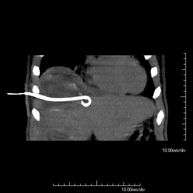

- CT-guided abdominal FNA (fine needle aspiration)

It consists in obtaining a tissue sample from a specific lesion located in the abdominal cavity. This test is performed using local anaesthesia on the puncture area, which is administered with fine-gauge needles. The entire procedure is monitored using images obtained by computed tomography (CT) at various stages of the puncture, using fluoroscopy-CT equipment. After the test, the patient remains under observation in hospital for a few hours. Coagulation tests must be performed before the puncture.

- CT-guided abdominal biopsy

It consists in obtaining a tissue sample from a specific lesion located in the abdominal cavity. It is sometimes performed under sedation with the help of an anaesthesia team. Needles are used to draw a cylinder sample from the lesion to be studied, which is then sent to the Pathology Department for histological analysis. The entire procedure is monitored using images obtained by computed tomography (CT) at various stages of the biopsy, using CT fluoroscopy. After the test, the patient remains in hospital under observation. Coagulation tests must be performed before the puncture.

- CT-guided abdominal drainage (abscesses, collections)

It consists of placing a drainage catheter over a collection of fluid located in the abdominal cavity, with the intention of emptying as much of the collection as possible. The patient should keep the drain in place for a few days, usually until it is no longer productive. It is often performed under sedation with the help of an anaesthesia team. The entire procedure is monitored using images obtained by computed tomography (CT) at various stages of the test, using CT fluoroscopy. After the test, the patient remains hospitalised. Coagulation tests must be performed before the test.